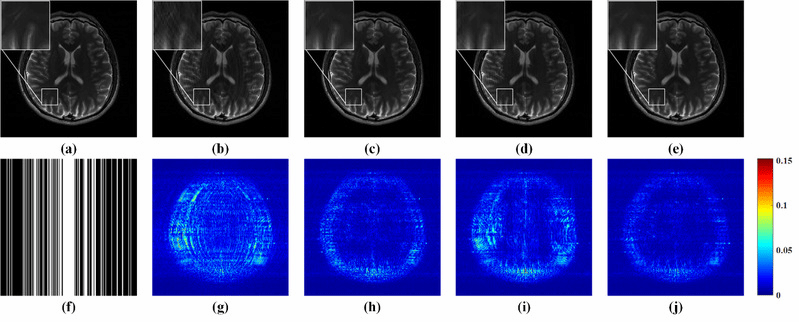

图2. 3倍加速下的4通道人脑数据重建结果及误差。(a)全采样数据参考图像;(b-e) GRAPPA、-SPIRiT、ALOHA和所提方法的重建图像;(f)3倍加速的采样模板;(g-j)相应的重建误差分布图。(b-e)图的相对二范数误差RLNE分别为:0.1335,0.0866,0.1117,0.0735。